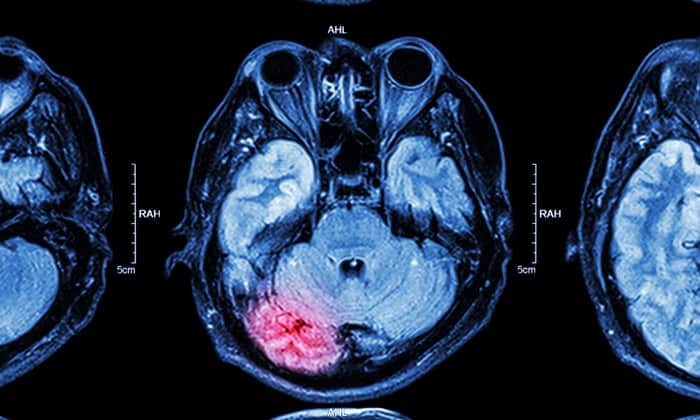

อาการบาดเจ็บที่สมอง (Traumatic brain injury หรือ TBI) สามารถเกิดขึ้นได้แบบไม่คาดคิด ซึ่งสามารถส่งผลทำให้ร่างกายพิการหรือถึงขั้นเสียชีวิตได้เลยทีเดียว อาการบาดเจ็บทางสมองนั้นสามารถเกิดขึ้นได้เมื่อสมองปะทะกับด้านในของกะโหลกศีรษะ ทำให้อาจมีรอยช้ำ มีเลือดออกในสมอง ทั้งยังอาจทำให้เส้นประสาทฉีกขาดได้อีกด้วย และถ้าหากรุนแรงมากขึ้นขั้นกะโหลกศีรษะแตก ส่วนที่แตกหักก็อาจจะไปเจาะเนื้อเยื่อสมองได้เช่นกัน

สมองของมนุษย์นั้นได้รับการปกป้องจากการกระแทกโดยน้ำไขสันหลังรอบๆ โดยสมองจะลอยอยู่ในของเหลวนี้ ภายในกะโหลกศีรษะ การกระแทกอย่างแรงที่ศีรษะส่งผลให้สมองเข้าไปกระทบกับกะโหลกศีรษะอย่างรุนแรง จนนำไปสู่การฉีกขาดของเส้นประสาท และมีเลือดออกในสมองรอบๆ นั่นเอง